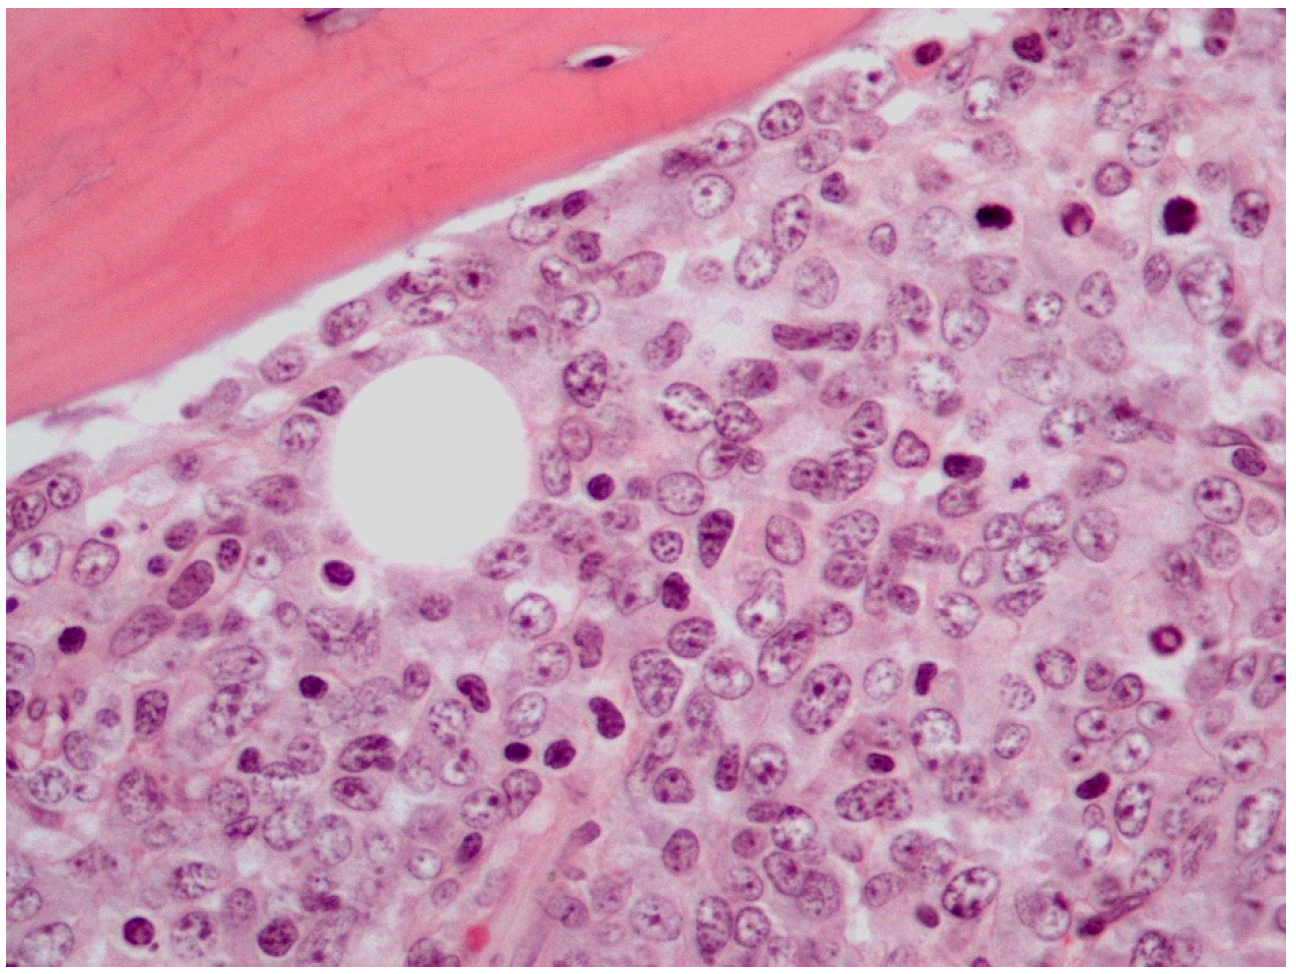

The majority of PB-DLBCLs, NOS exhibit a diffuse growth pattern (Figure 1) [8,18,72]. The neoplasm consists of large, atypical cells or a polymorphous mixture of small to large cells with multilobulated nuclei, fine chromatin and an unobtrusive to prominent nucleoli in a background infiltrated by mature T-cells [2,8,18,27,72]. The bone trabeculae can appear normal or thickened. Delicate reticulin fibrosis and occasional diffuse fibrosis are observed between the cells. This lymphoma may uncommonly display immunoblastic morphology, which is characterized by abundant amphophilic cytoplasm and round nuclei with prominent nucleoli. Additionally, PB-DLBCL, NOS may rarely contain clear cytoplasm cells and signet ring cells, thus mimicking metastatic adenocarcinoma [72]. An extremely unusual morphology of PB-DLBCL, NOS is the spindle cell variant, which can be misdiagnosed as sarcoma or carcinoma [23,72]. It has been reported that lymphoma cells may obtain a spindle morphology as they infiltrate into osseous and soft tissues. Furthermore, it has been hypothesized that the lymphoma cells mediate their spindling process by secreting specific cytokines, including TNF-α, platelet-derived growth factor (PDGF) and transforming growth factor (TGF) -β [23]. These cytokines induce fibrosis and proliferation of fibroblasts, which may impinge on neoplastic cells compressing them into a spindle shape [23,72].

Figure 1.

Histological features of PB-DLBCL, NOS (Hematoxylin-Eosin staining, 600× magnification).